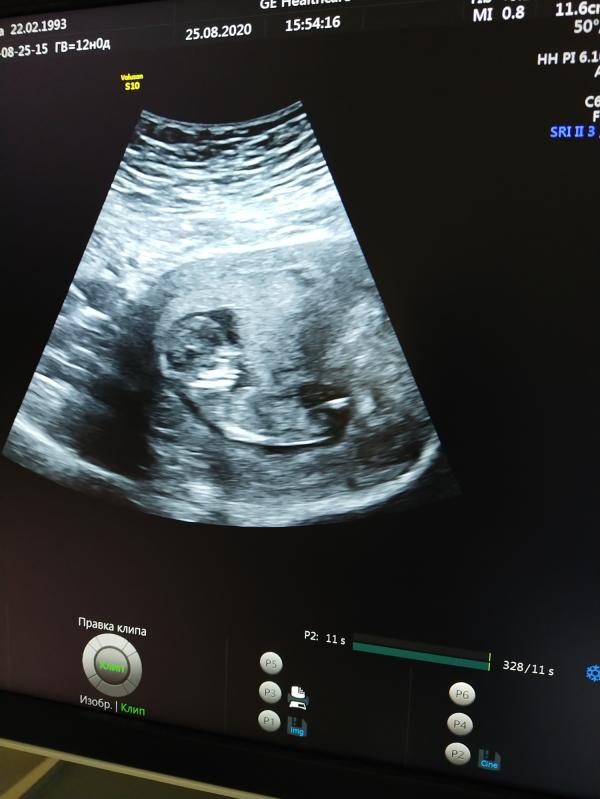

На 20 неделе "вызываем роды,пишите бумагу ,отстает в весе,миома ,на ней плацента.он умрет в родах или в Вас"

Я не перестаю удивляться как мы были правы... 39 неделя весом 2 килограмма и 45 см появился наш Сережа.на утро 1800

Я не знаю ,что случилось со мной в момент,когда мне протянули ту бумагу с заключением УЗИ в монииаг ,он толкнулся и я поняла все без слов просто ушла и муж все понял по глазам когда я вышла (в монииаг не пускают мужчин) он сказал что он наш ребенок и только нам решать ,а раз мы подарили ему жизнь ,значит все в наших руках до конца

Да,что вес не соответствует гестации и животик отставал и на миоме плацента была и она отнимала питание поступающее к ребенку